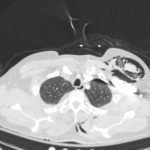

A 52-year-old male presented to the emergency room with left chest wall pain and upper back pain after falling from an estimated height of 24 feet, landing on his back. On physical exam, the patient had crepitus to left chest wall and back and was persistently hypotensive in the trauma bay.

Plain film anteroposterior (AP) radiography of the chest shows left-sided subcutaneous emphysema (red arrow) with overlapping muscle striations of the pectoralis major (green arrow). After chest tube placement (blue arrow), AP chest radiography shows persistent left-sided subcutaneous emphysema (red arrow). CT of the chest shows pneumomediastinum (blue arrow), left apical pneumothorax (pink arrow), and subcutaneous emphysema (red arrow) at the level of T2. At the level of T6, rib fractures can be visualized on the CT (yellow arrow). At the level of T8, left sided pneumothorax is also seen (pink arrow) as the absence of lung tissue on CT.

Injuries of the thorax account for 25% of all mortality in trauma patients, of which many are preventable deaths by simple interventions.1,2 One sign commonly seen in patients with chest trauma is subcutaneous emphysema. The presence of this underlying emphysema has been suggested to be a sign of injury to the respiratory tract, making it clinically significant.3,4 Specifically, subcutaneous emphysema has been shown to be a clinical predictor of occult pneumothorax, with an odds ratio of 5.47.3 Furthermore, these injuries to the respiratory tract (pneumothorax /hemothorax, pneumomediastinum, etc.) can lead to hemodynamic instability and respiratory failure.4-6

Treatment of these injuries consist of different measures. Subcutaneous emphysema does not usually require treatment and will reabsorb spontaneously.7 Pneumothorax and hemothorax are both treated with chest tube placement. In a hemothorax, however, if the tube evacuates more than 1,500 mL of blood immediately or more than 200 mL/hour, the patient should be taken to the operating room for surgical exploration of the chest.8 Therefore, complete investigation into the underlying cause of subcutaneous emphysema is essential in managing patients with chest trauma.

In this patient, given the findings of multiple bilateral rib fractures, bilateral hemothorax/pneumothorax and multiple spine fractures, bilateral chest tubes were placed which had immediate output. The patient was admitted to surgical intensive care unit for chest tube management, pulmonary hygiene and further management of his other injuries.